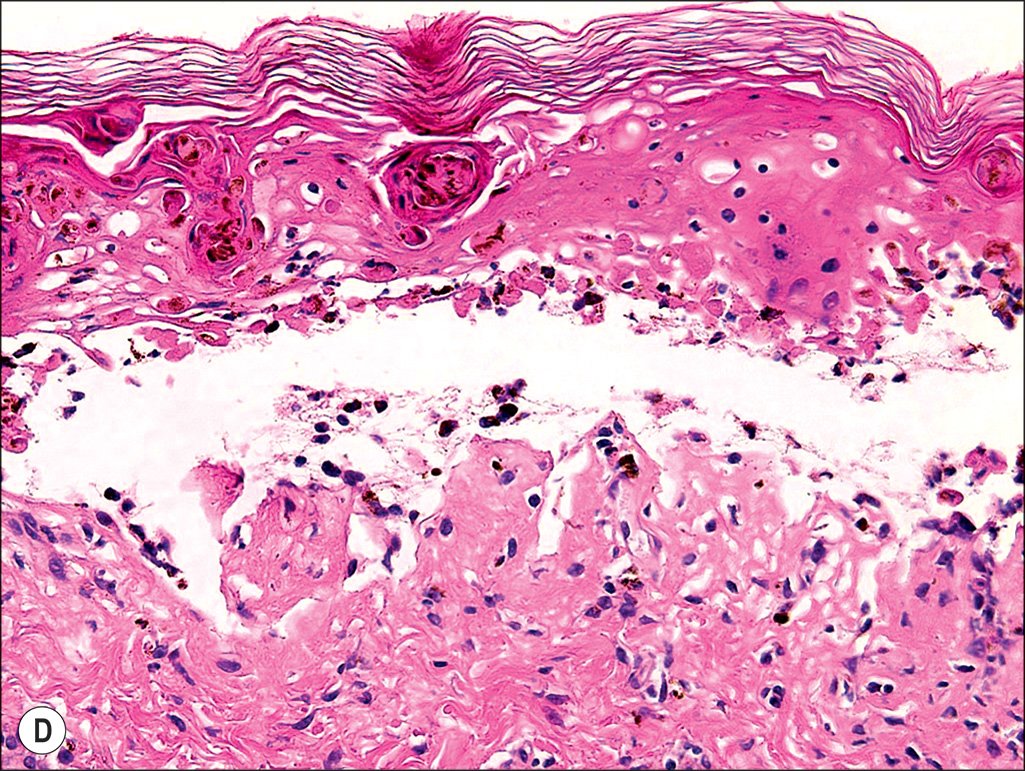

Toxic shock syndrome (TSS) rash. Cutaneous rash commonly seen in patients with TSS. This rash does not universally appear in cases of TSS. Patients with small burns developing shock should be evaluated and treated for TSS with excision, grafting, and vancomycin. (A) A 13-year-old girl presenting TSS rash following a 10% total body surface area burn. (B) The typical macular erythroderma lesions. (C) A hematoxylin and eosin (H&E) 4× magnification micrograph of a TSS rash lesion showing an epidermal blister. (D) Further H&E 40× magnification micrograph with low inflammation.

(From Omar P. Sangüeza, MD; Professor and Director of Dermatopathology, Wake Forest University School of Medicine, North Carolina.)